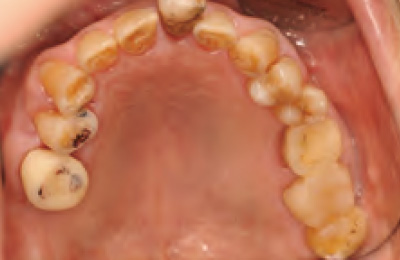

臨床でしばしば遭遇するフレアリングケース。

治療結果の品質向上に対して、矯正の貢献度は高い。